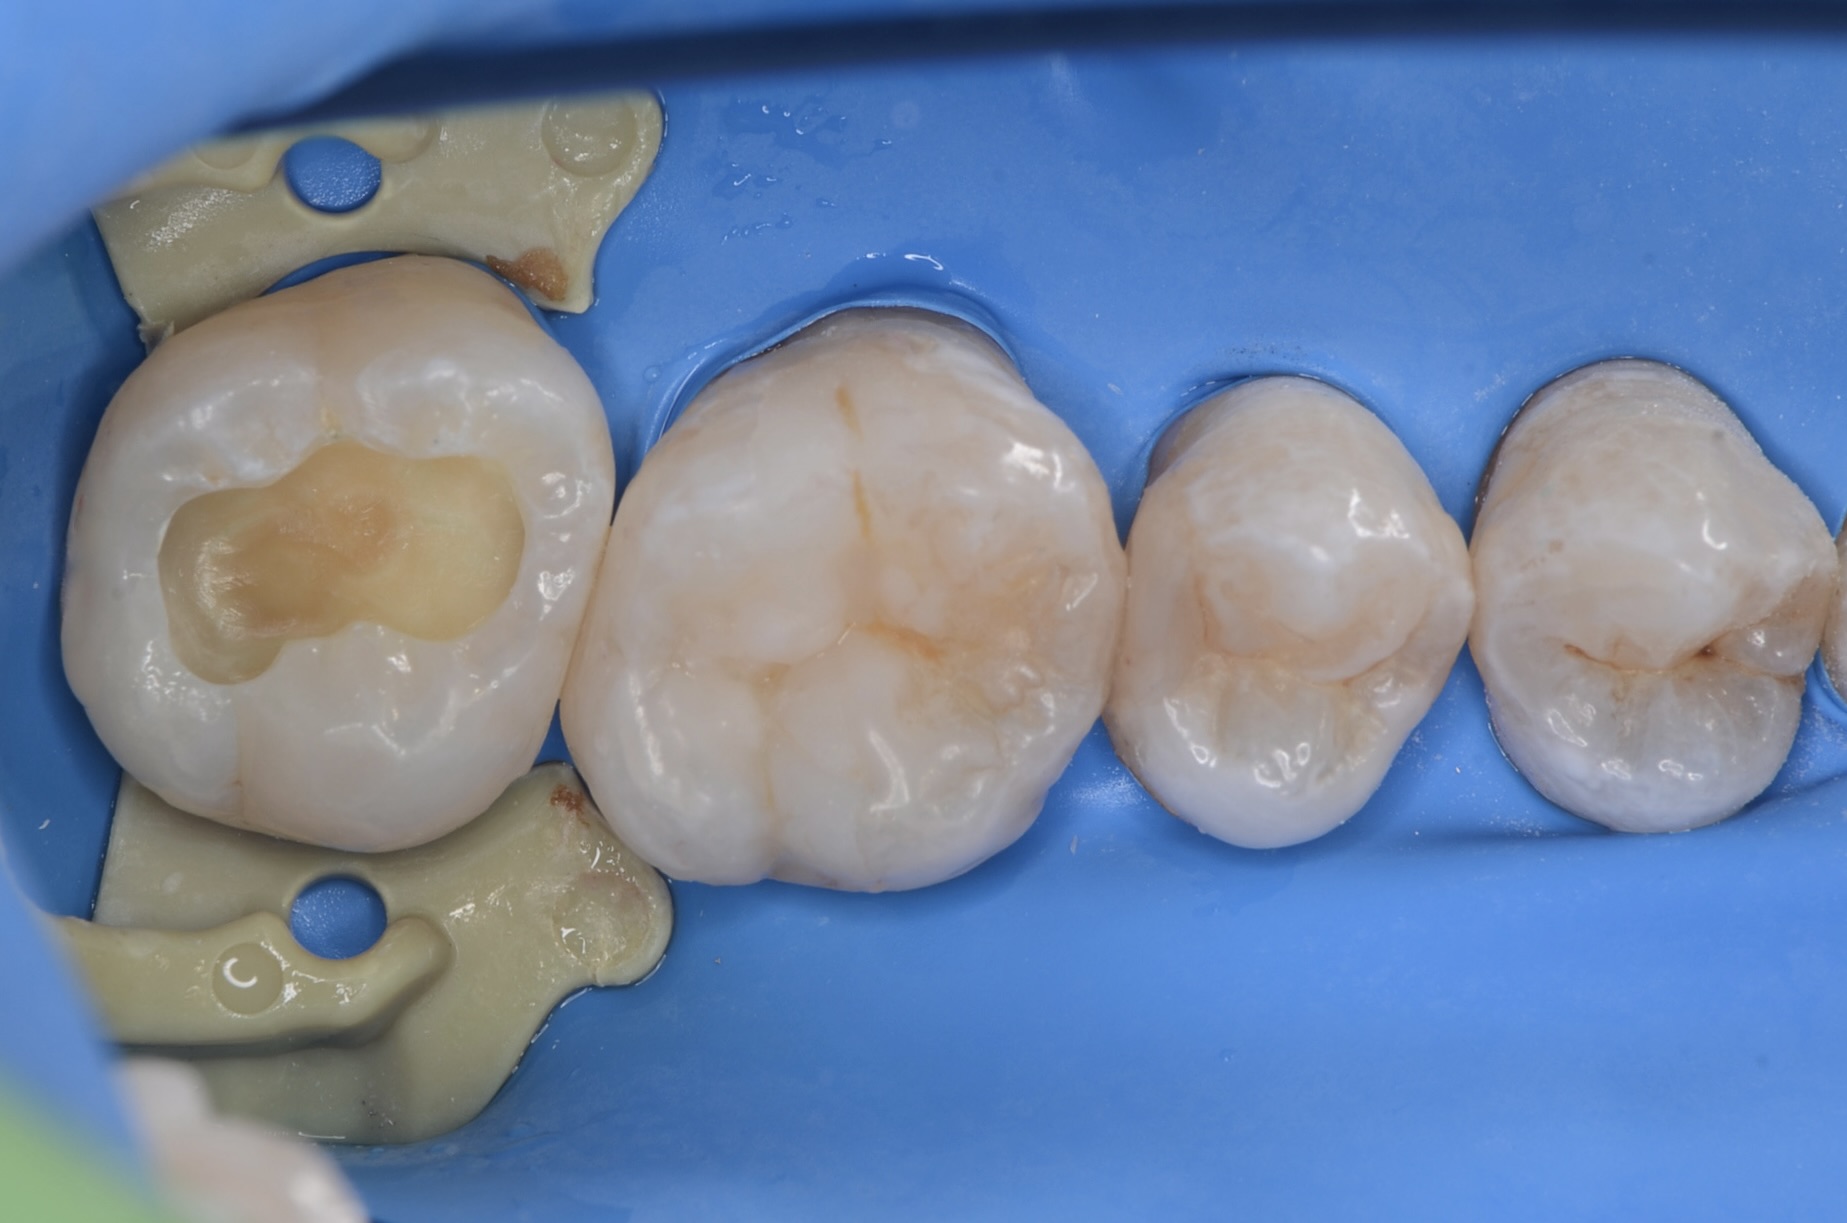

知覚過敏抑制材

虫歯を削った後は、知覚過敏抑制材を刷り込みます。 -

ダイレクトボンディング

象牙質の範囲まで、濃い目の色のレジンを充填します。中の色を濃くしておくと、最終的に僅かに透けて立体感が出ます。 -

充填完了

天然歯の形態を模倣して滑らかに仕上げました。 -

1週間後研磨

歯垢が付きにくいように、歯と歯の間、歯とレジンの境目を丁寧に研磨します。 -